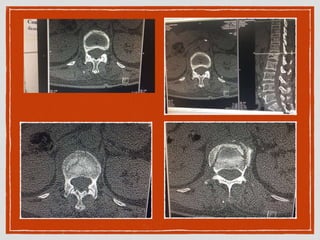

CT TL spine

comminuted fracture of anterior and

posterior vertebral body L1,

40% anterior height collapse of L1,

burst fracture with fracture L1 spinous

process

no retropulsion of bone into spinal canal

the rest of spine no visualised fracture and

spondylolisthesis

degenerative change of lumbar spine is

seen

Admit Bed rest Pain control CTTL spine comminuted fracture of anterior and posterior vertebral body L1, 40% anterior height collapse of L1, burst fracture with fracture L1 spinous process no retropulsion of bone into spinal canal the rest of spine no visualised fracture and spondylolisthesis degenerative change of lumbar spine is seen